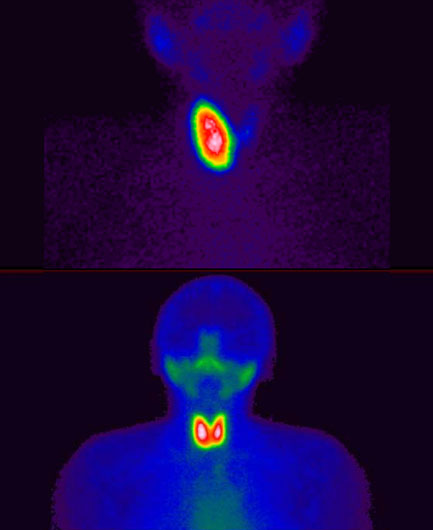

131I-Yodo radiactivo

- Hipertiroidismo

- Cáncer de Tiroides

Gammagrafía

- Tiroides

- 131I-Yodo radiactivo

Yodo radiactivo

Yodo radiactivo (Yodo131; I-131; 131I)

Hipertiroidismo

Cáncer de tiroides